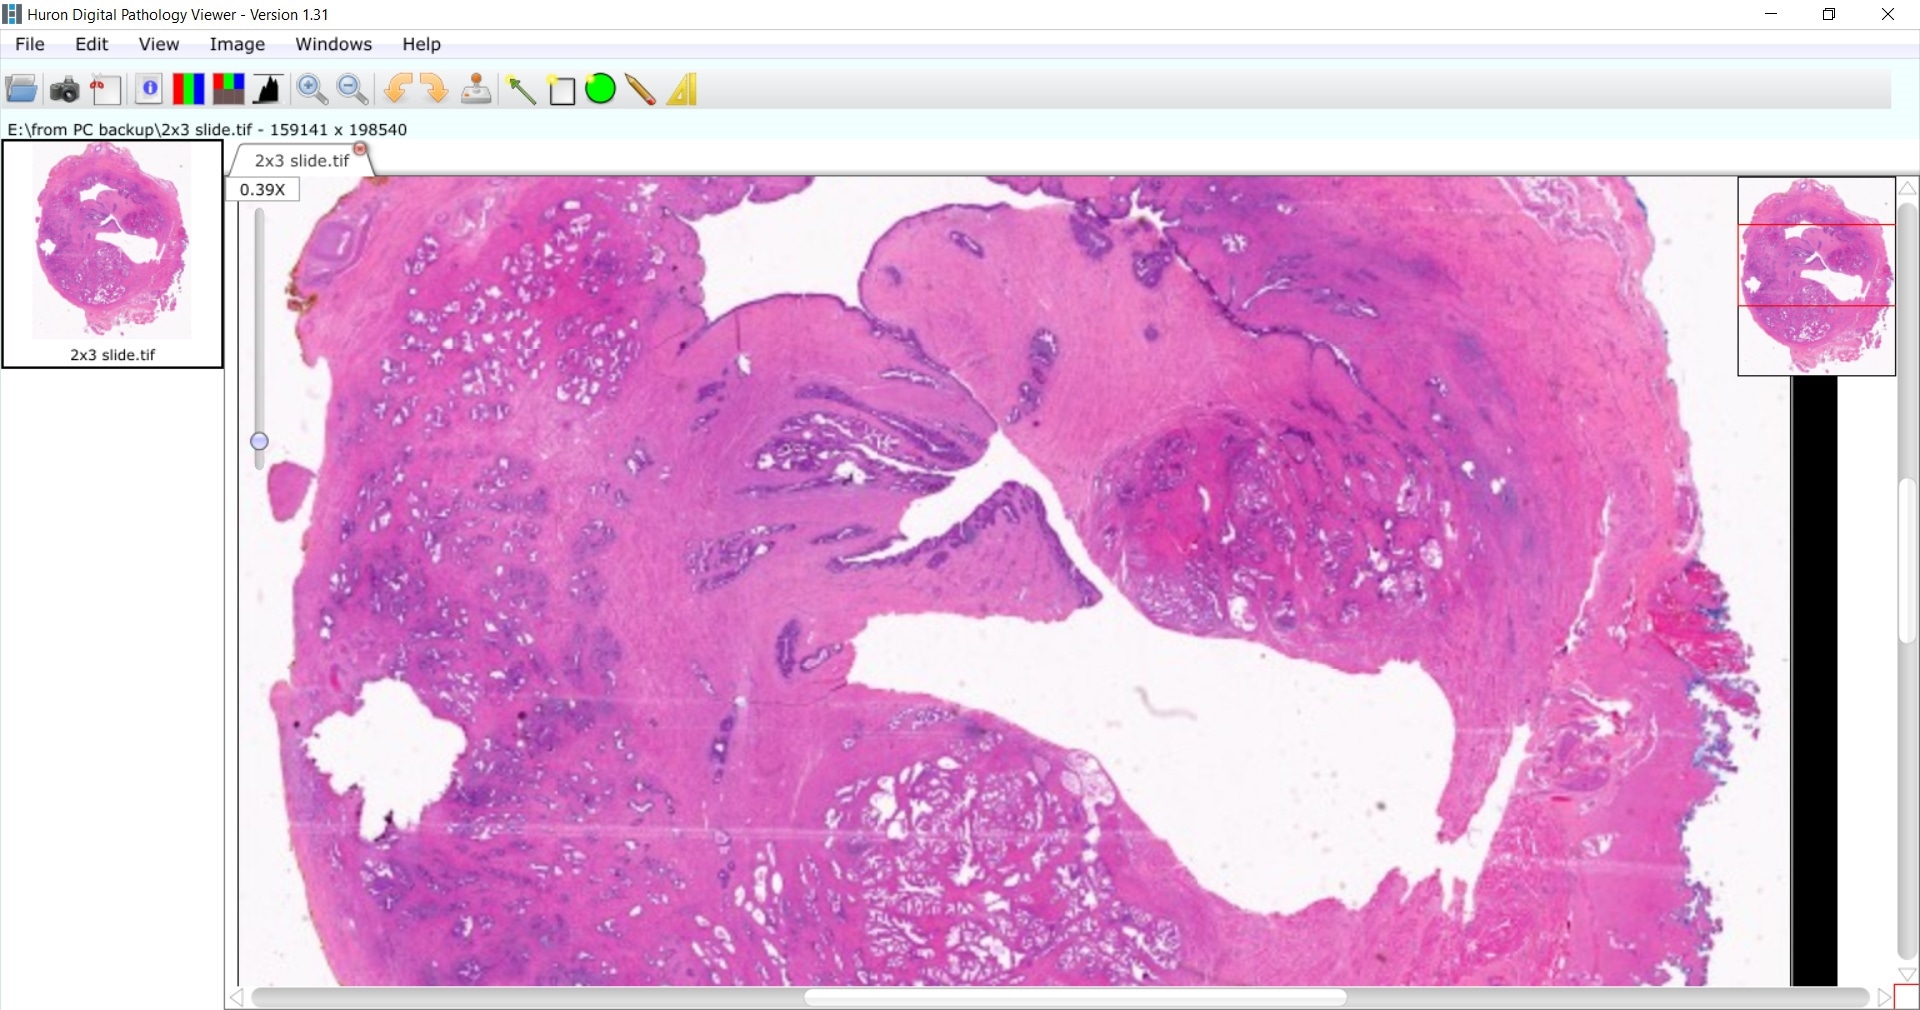

prostate cancer sample

Image credit: Huron Digital Pathology.

Our goal is to find better predictors of outcomes, such as the microenvironment of the cancer, how the cancer is growing in the stroma or what surrounds the prostate cancer cells. We would like to see if there are any unique signatures that we can decipher in this digital image.

Also, within a prostate biopsy, there might be benign mimickers of cancer, which can lead to misdiagnosis of cancer and overtreatment. We would like to find diagnostic features in the digitized slide that will help us separate the benign mimickers from variants of prostate cancer.